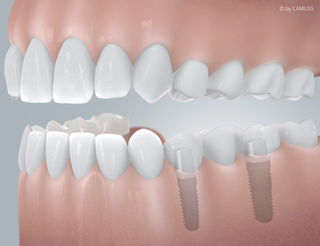

OH JE, EIN ZAHN FEHLT

Schnell kann es gehen!

Ein Unfall beim Sport oder ein Sturz im Alltag und plötzlich fehlt ein Zahn. Implantate sind hier eine schnelle und einfache Lösung – “naturnah” und unsichtbar. Fühlt sich an wie Ihr natürlicher Zahn und funktioniert auch genau so. Die kleinen und leistungsstarken Titan-Schrauben von Camlog übernehmen die Aufgaben Ihrer ursprünglichen Zahnwurzel. Darauf wird Ihre neue individuelle Zahnkrone befestigt. So ist alles wieder an seinem Platz – ganz natürlich, als wäre nichts gewesen.

Sind Implantate einmal eingesetzt, nehmen sie genau die Position Ihres natürlichen Zahns ein. Insbesondere auch da, wo es nicht direkt sichtbar wird: Camlog Implantate sind der natürlichen Zahnwurzel nachempfunden. So werden Knochen und Zahnfleisch richtig belastet und ausgeformt. Gesunde Zähne bleiben grundsätzlich unberührt und müssen nicht wie bei einer festsitzenden Brücke abgeschliffen werden. Es sind auch keine Metallklammern um benachbarte Zähne als zusätzliche Befestigung nötig, wie beispielsweise bei herausnehmbaren Teilprothesen. Bei Implantaten ist all dies überflüssig – eben rundum eine gelungene Lösung.

Befund

Auffällige Zahnlücke: Nach Zahnverlust

Versorgung

Lückenlos versorgt, mit einem Implantat